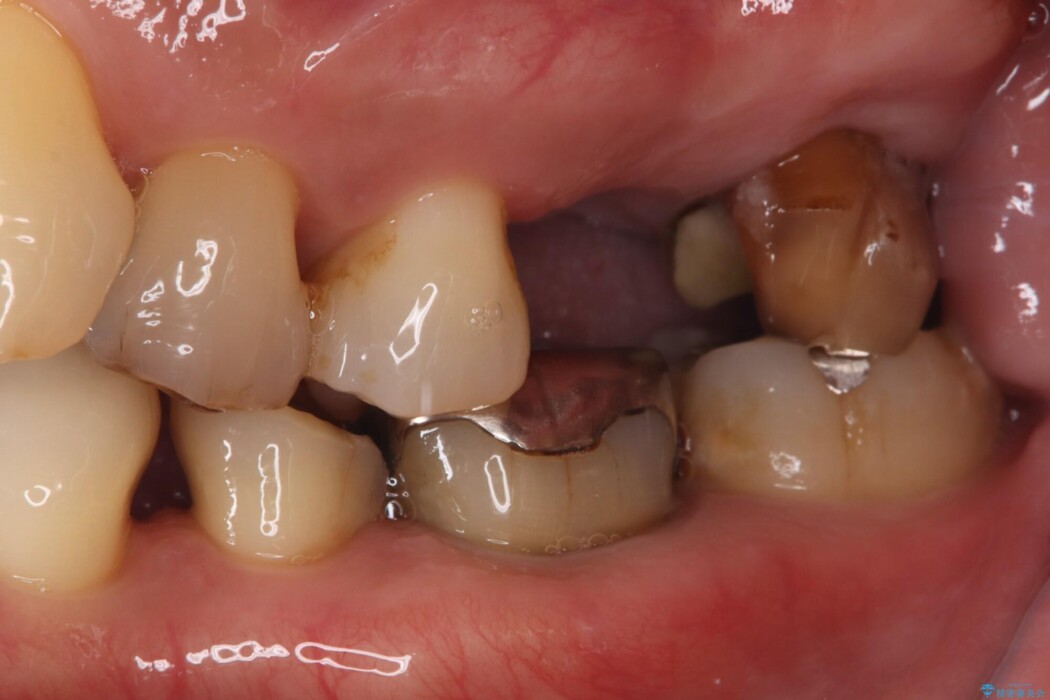

過去に治療を中断し、そのままにしていた左上奥歯の治療をしたいとご来院されました。

精密検査の結果、治療を中断していた左上7番は重度の虫歯や歯周組織の崩壊により保存が難しい状態でした。

6番も歯を失ってから時間が経っていたため、奥歯でしっかりと噛むことができない状態でした。